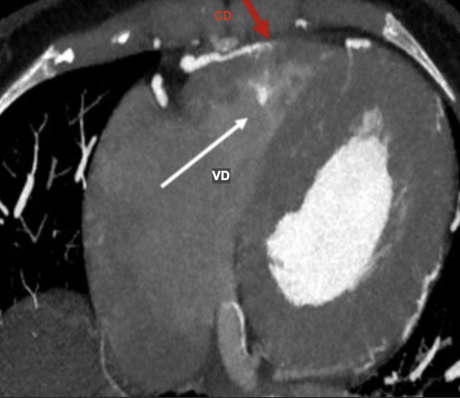

Fistule CD-Atrium Droit massive avec thrombus, secondaire a une erosion d’angiosarcome